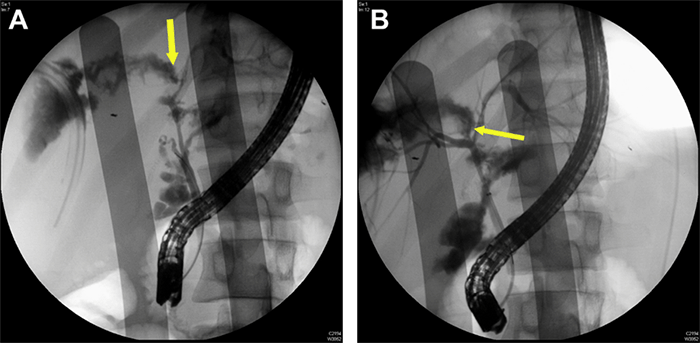

Biliary sphincterotomy was performed, and an 8.5F by 7 cm plastic transpapillary biliary stent was placed in the common bile duct (CBD). Despite stenting, he continued to have high bilious output from his drains (approximately 600 cc/day); interventional radiology performed percutaneous transhepatic cholangiography (PTC), showing a persistent large bile leak at the hepatic duct bifurcation (Figure 4). An 8.5F percutaneous transhepatic biliary drain (PTBD) was placed across the leak with a distal tip within the duodenum. During this time he also required treatment for recurrent ESBL-producing Escherichia coli bacteremia that was cultured from an intra-abdominal abscess and the bile in his PTBD. The bilious drainage decreased significantly over the next month after discharge, and the drain was subsequently removed in the clinic.

Figure 4. Percutaneous Transhepatic Cholangiography Showing Persistent Bile Leak at Bifurcation. Published with Permission